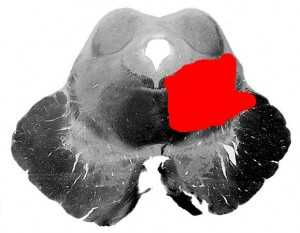

Один из педункулярных альтернирующих синдромов ствола мозга. Возникает при поражении волокон глазодвигательного нерва, красного ядра, медиального продольного пучка и латеральной петли.

Субстрат поражения и клинические симптомы:

Клинические проявления синдрома Нильсена имеют несколько вариантов. В частности, возможен изолированный синдром опсоклонуса или синдром двухстороннего снижения слуха.